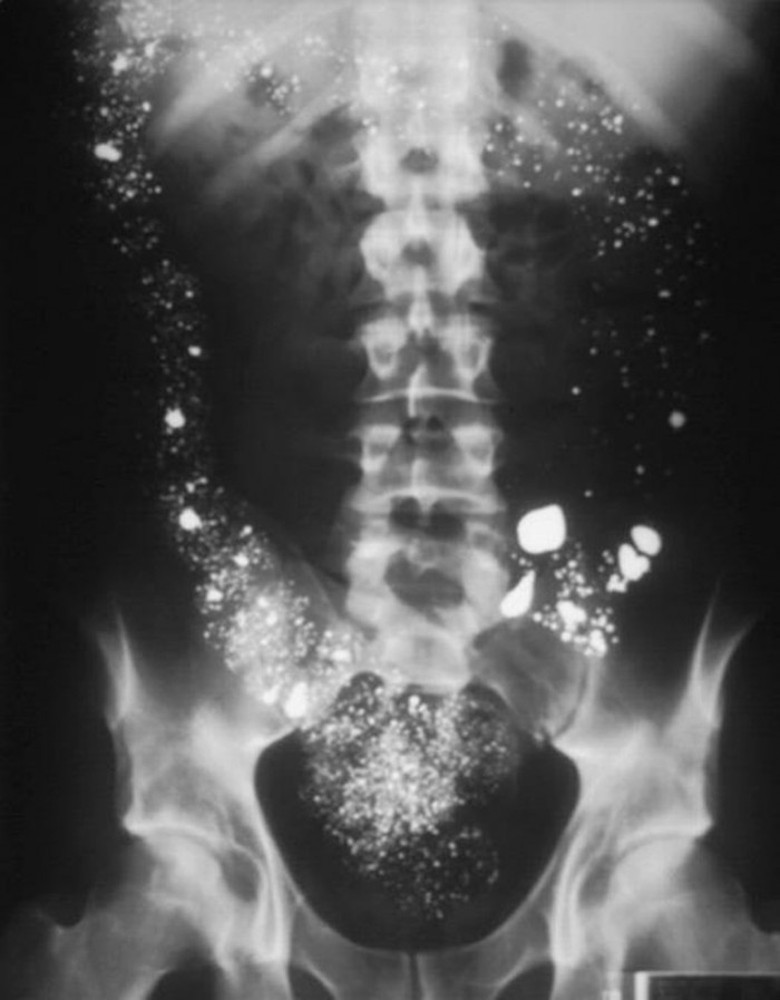

Kết quả chụp X-quang của một bệnh nhi cho hình ảnh nhiều chấm cản quang rải rác, chính là những hạt thủy ngân nằm trong cơ thể